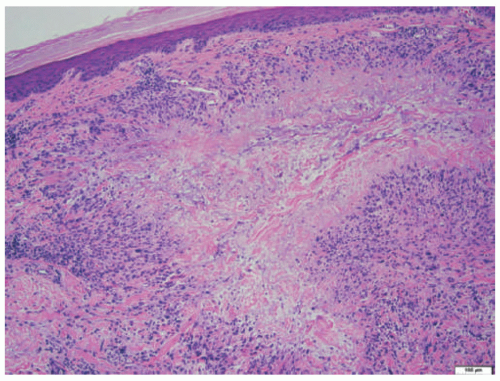

EN is the prototypical septal panniculitis, characterized histologically by a widening of, and inflammation in, the subcutaneous fat septae, with associated septal fibrosis. One often appreciates “spill-over” inflammation into the surrounding fat lobules as well, but low-power microscopic examination usually clearly demonstrates septal involvement as the primary process. The inflammatory cell infiltrate is composed of lymphocytes and histiocytes (Figure 5-2). In acute disease, a varying number of neutrophils and eosinophils are often present, and vasculitis may rarely be noted. Small granulomas formed by the aggregates of histiocytes surrounding a central cleft (so-called Miescher’s radial granulomas) are often present; they are common in, but not pathognomonic for, EN, and can be seen in other forms of panniculitis, as well as in neutrophilic dermatoses and necrobiosis lipoidica (NL) diabeticorum.4,5

![]() FIGURE 5-2. Erythema nodosum histopathology: widening and chronic inflammation of the subcutaneous fat septae. |